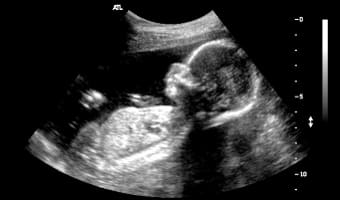

Вероятность перепутать кисту с беременностью во время УЗИ

Отличить оплодотворенную яйцеклетку от кистозного образования может даже врач-новичок. На ультразвуковом исследовании эмбрион становится видимым уже на третьей неделе беременности, а его сердцебиение можно услышать на шестой неделе. Поскольку женщины обращаются на УЗИ при длительной задержке менструации, вероятность ошибки в диагностике сводится к минимуму.

Что касается кист, то они обладают характерными патологическими признаками, которые позволяют точно установить диагноз. Поэтому вероятность перепутать кисту с оплодотворенной яйцеклеткой крайне мала.

Тем не менее, в медицинской практике встречались случаи, когда первоначально поставленный диагноз кисты позже изменялся на беременность. Однако такие ситуации являются редкими.